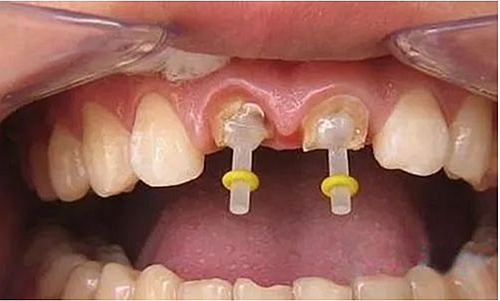

患者右上前牙因外傷冠修復(fù)體脫落來我院找口腔修復(fù)科金小婷醫(yī)師治療。經(jīng)檢查,患者剩余牙體組織少,經(jīng)溝通確認后,進行上前牙全瓷冠修復(fù)。

△材料充填后牙體預(yù)備